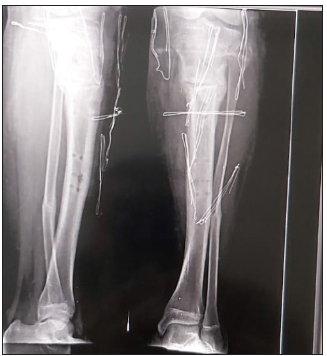

After radiological healing, the nuts were loosened to be sure of clinical healing and to avoid refracture then frame removed after one week. Two patients had under correction and were adjusted at the first follow up. In patients having residual limb length discrepancy, distraction osteogenesis was started two weeks postoperative one mm per day till obtaining equal length. In patients with adjustment of the frame postoperative, long X ray film and CT scanogram was repeated. Frame removal was done under sedation. Above knee cast was applied in patients weighting more than 100kg. X ray film of the knee and tibia was done after frame removal (Figure 3 )The average time of follow up was 9 months (range 5-13).

Figure 3: Showing AP and lateral radiographs of knee and leg after frame removal, with good healing and alignment.